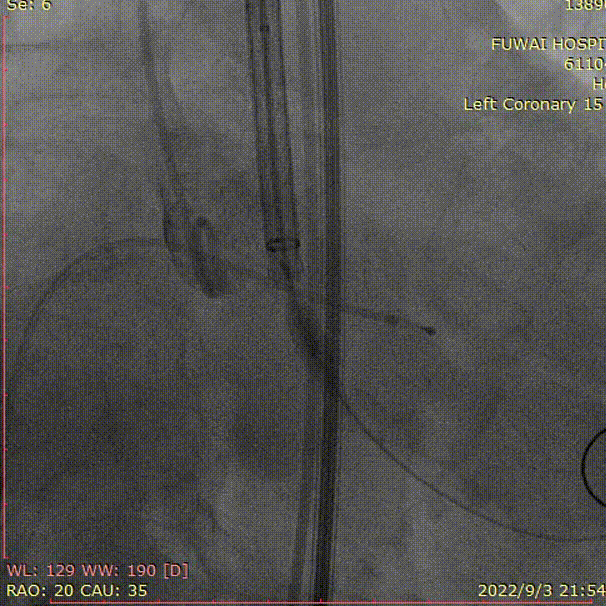

1、冠脉造影和抉择急诊PCI和急诊TAVR

左冠造影